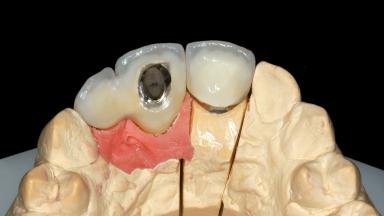

Replacement of an Upper Right Central and Lateral Incisor with an Implant-Supported Crown and a Distal Cantilever

Prosthesis Type FDP

Abutment Type Customized